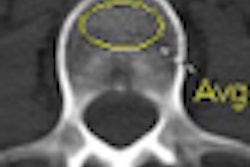

![]() |

| In a cohort of 30,000 patients, mean adenoma detection rate (ADR) was 34% of patients using the supervised primary care physician model (blue dots). In comparison, green, yellow and red dots show three tiers of lower adenoma detection rates from 12-board certified gastroenterologists in a 2006 analysis of colonoscopy performance. The U.S. national average ADR is 20% of Image courtesy of Stephen Lloyd, MD, PhD. |

The big question, according to Lloyd, is "if we get them to improve compliance and address capacity, what's going to happen to the quality?" The answer is that it has soared, he said. In 30,000 cases, the average adenoma detection rate (ADR) was 34% of patients, compared to a U.S. national average of 20%.

According to the results, compliance more than doubled -- from 38% to 84% -- when the primary care physician performed the colonoscopy, Lloyd reported. The gross completion rate (the rate at which the colonoscope reached the cecum) was 98.3%. The adenoma detection rate was 34%. Complications were the lowest ever reported.

"We've augmented the capacity so that we can get to where we can screen 80% of the population and the quality is outstanding," Lloyd said. "Our adenoma detection rate is 34% and the national average is 20%."